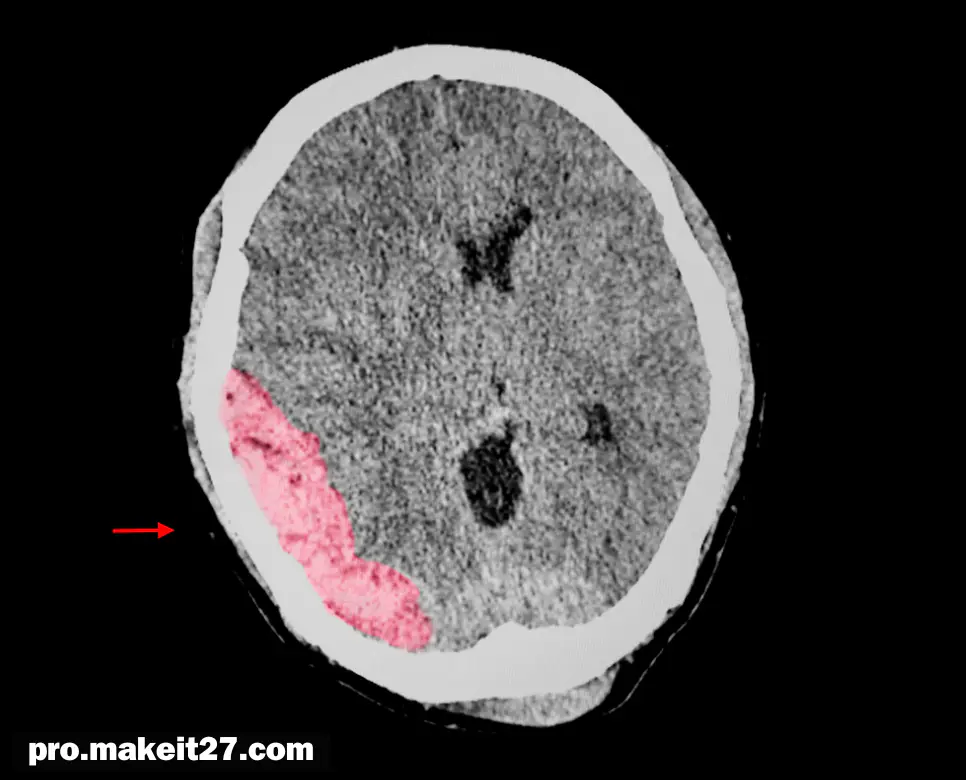

- 진단 방법: TBI의 진단은 주로 신경학적 검사와 의료 영상을 기반으로 이루어집니다. 신경학적 검사에서는 의식 수준, 기억력, 집중력, 운동 및 감각 기능 등을 평가합니다. 의료 영상으로는 CT 스캔이 가장 흔히 사용되며, 두개내 출혈, 뇌 좌상, 두개골 골절 등을 확인할 수 있습니다. 경미한 TBI의 경우 CT 스캔에서 이상이 발견되지 않을 수 있으므로, 증상과 임상 소견을 종합적으로 고려하여 진단합니다.